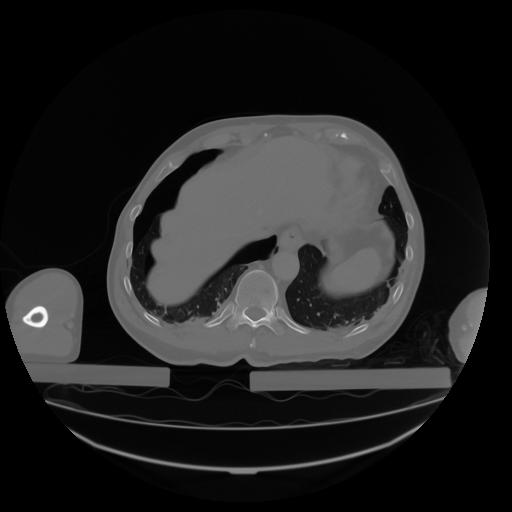

27 CUERPO,CE,Axial,3.0,CUERPO,,